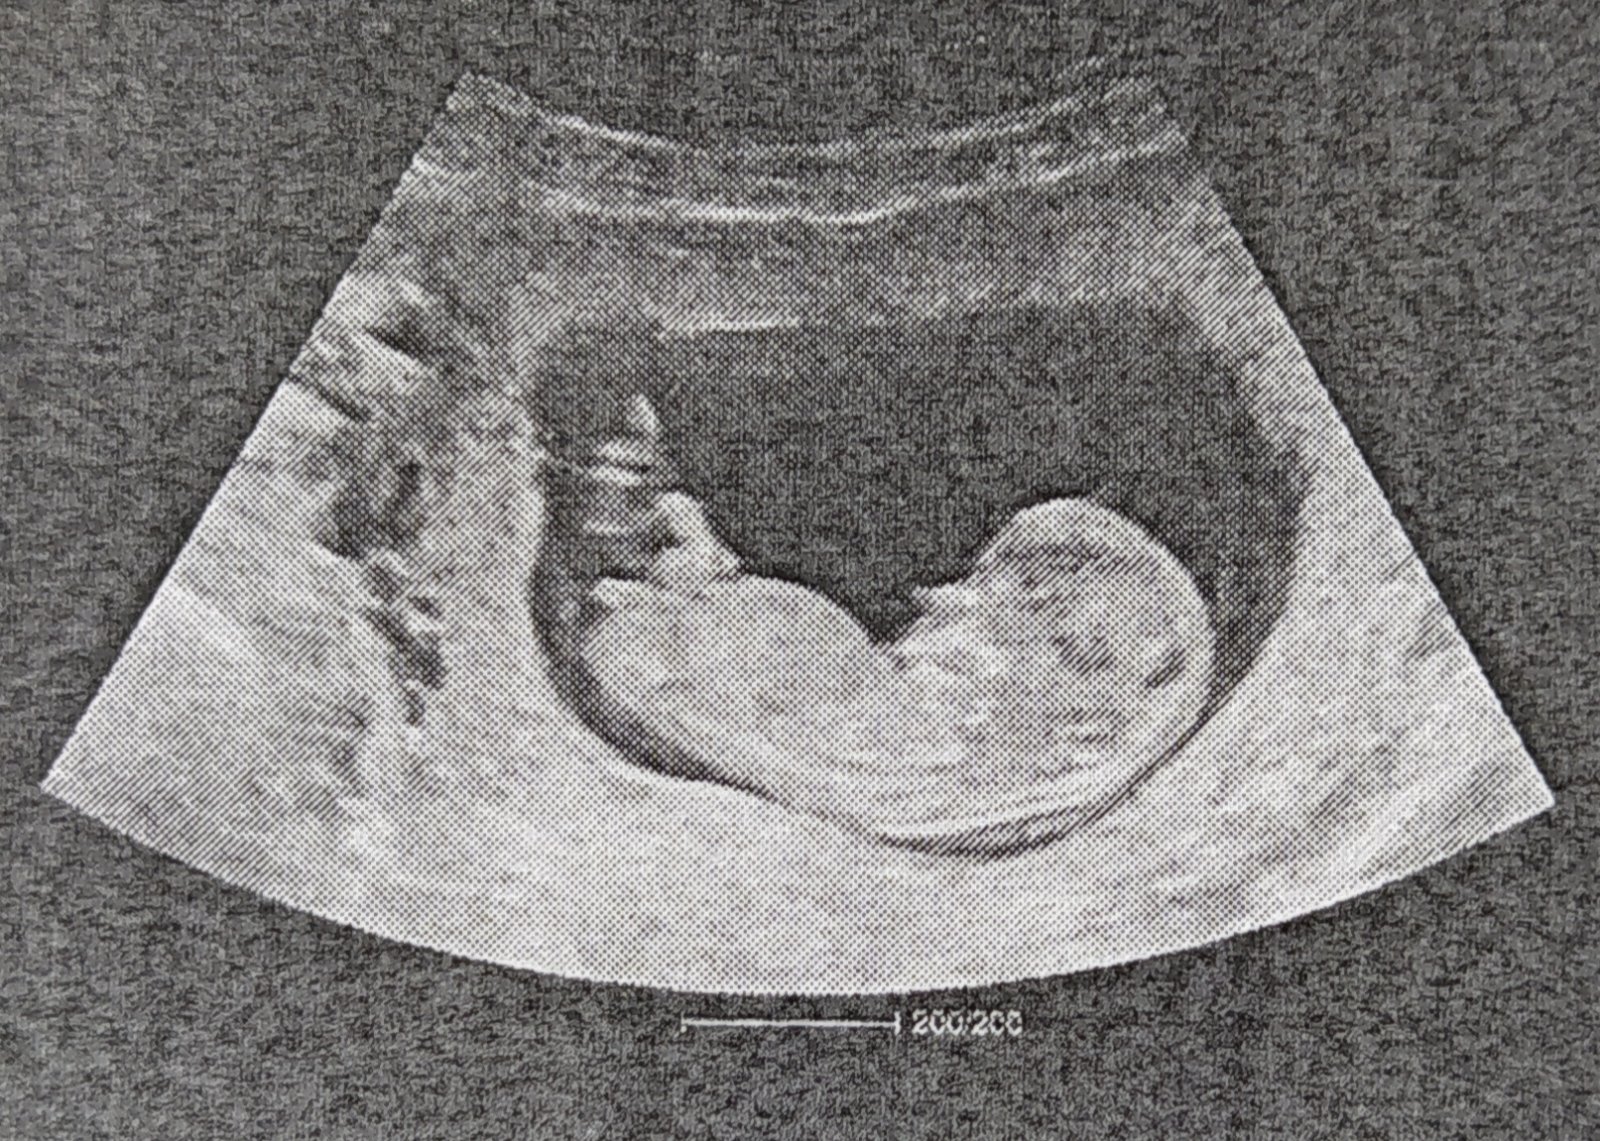

Maly odkaz pre niekdajsie spolubojovnicky z tejto temy... bude surodenec... Drzte paluchy 🙏